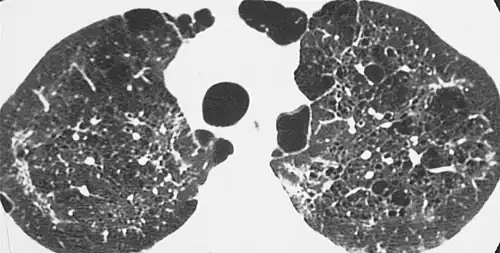

- A lung cyst has a wall thickness of up to 4 mm.[2] A minimum wall thickness of 1 mm has been suggested,[2] but thin-walled pockets may be included in the definition as well.[5]

Lung cysts are seen in about 8% of the general population, with an increased prevalence in older people, and are not associated with emphysema.[5] They may be part of the aging changes of the lungs, and cause a slight decrease in their diffusing capacity.[5] The presence of multiple pulmonary cysts may indicate a need to evaluate the possibility of bullous or cystic lung diseases.[5] Cavitation indicates workup for serious infection or lung cancer.

Cyst

A pulmonary cyst is not necessarily the same type of cyst seen in many cystic lung diseases. The cyst for example in pneumocystis pneumonia is not the same as the pulmonary cyst.

Cystic lung diseases include:

- Langerhans cell histiocytosis (LCH)[5]

- Lymphangioleiomyomatosis (LAM)[5]

- Lymphocytic interstitial pneumonia (LIP)[5]

- Birt–Hogg–Dubé syndrome[7]

- Pneumocystis pneumonia[7]

- Pulmonary amyloidosis[7]

- Light chain deposition disease[7]

- Lung metastases rarely cause multiple cystic lung lesions. This form of presentation has been described in metastatic sarcomas.[7]